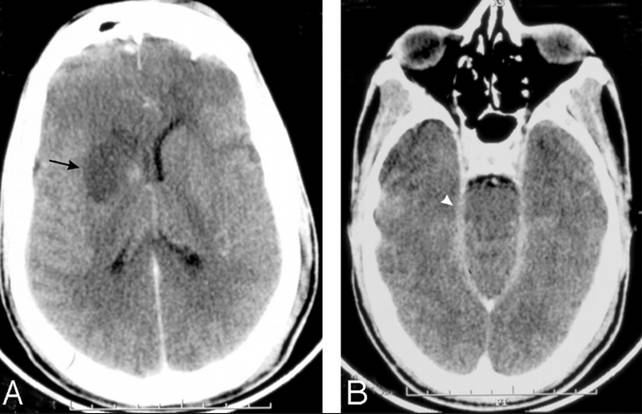

Hình 1

Hình 2